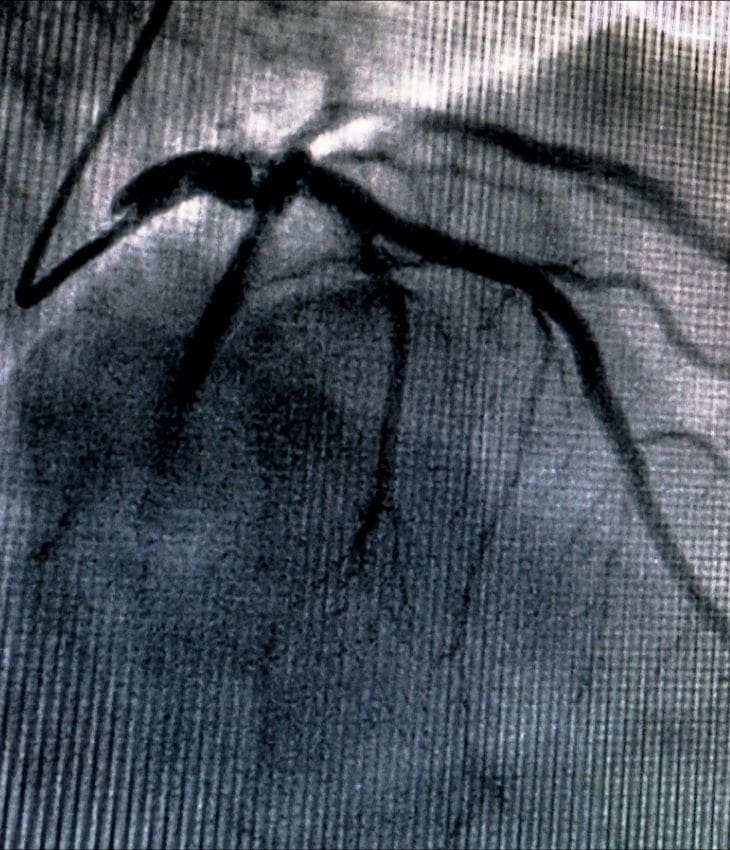

Advanced imaging refers to specialised, high-resolution scans used to assess the heart and blood vessels in greater detail than basic diagnostics allow.

At Dr Sen’s clinics, these include cardiac MRI, CT coronary angiography, and echocardiography with Doppler analysis. These tests help visualise heart anatomy, blood flow, valve function and coronary artery disease. They are often used to confirm a diagnosis, guide treatment decisions, or monitor progress in patients with known or suspected cardiac conditions. All imaging is performed in partnership with top-tier diagnostic centres for maximum accuracy.

- Suspected coronary artery disease: To detect narrowed or blocked arteries non-invasively using CT coronary angiography.